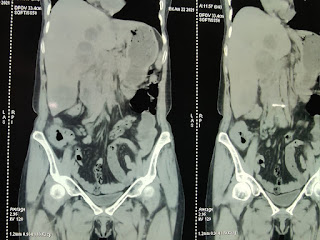

Pt went to miryalaguda care hospital I/V/O fever,decreased appetite on 17/6/21.usg abdomen showed mild hepatomegaly with multiple abcess

Multiple liver abcess

-MULTIPLE LIVER ABCESS